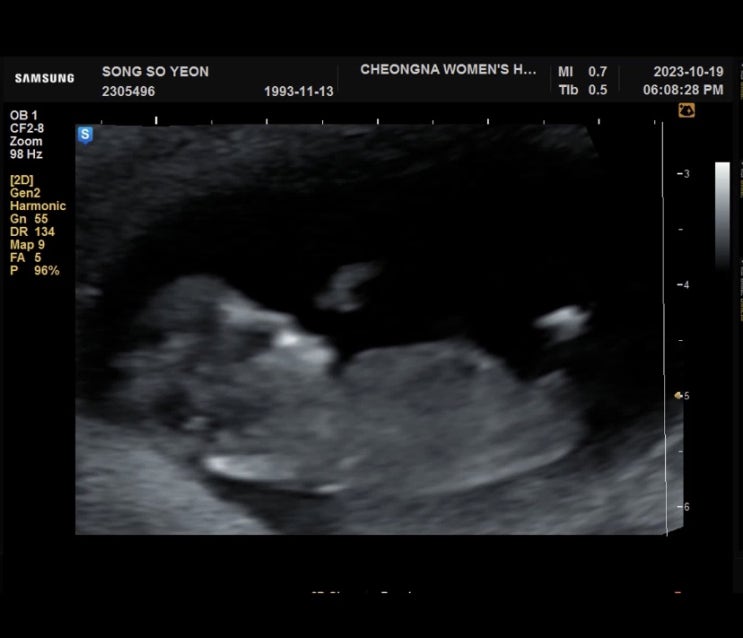

다솜이 첫만남

9/16일 첫만남 한번의 유산 다시 만난 소중한 아가 아프지말고 건강하게만 태어나다오 “애틋하게 사랑하는...

다솜이

10/19